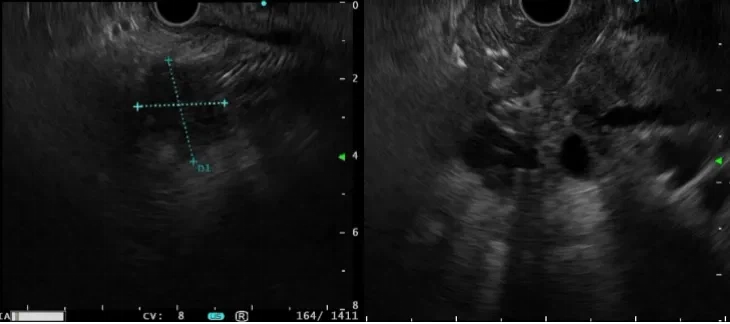

5. Maladies pelviennes et périrectales:L'EUS du rectum est particulièrement utile pour diagnostiquer les sarcomes abdominaux et peut inclure une biopsie pour obtenir des échantillons pathologiques.

▲ Sarcome abdominal